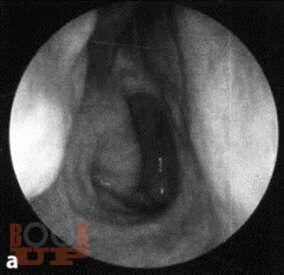

Описаны подробные методики исследования носа, околоносовых пазух, глотки, гортани и уха, а также основные диагностические и лечебные манипуляции.